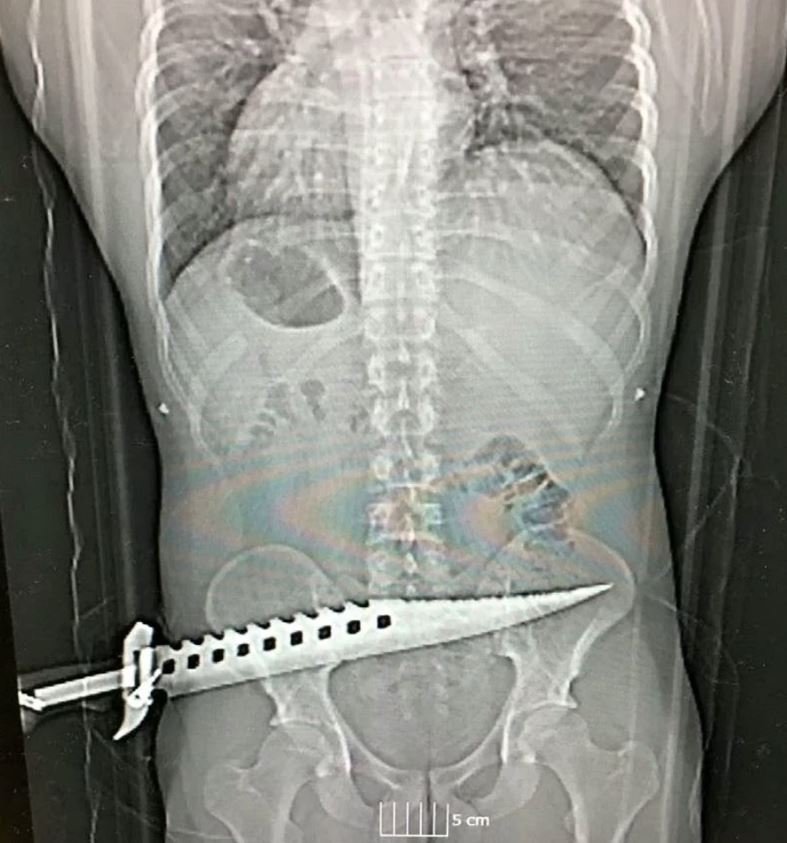

İntikam almak için saldıran Parker, dev boyutlardaki bir bıçağı adamın kalçasına sapladı. Parfitt'in hoşlandığı kadınla birlikte olan kurban olay yerinde güçlükle kaçabildi. Ambulansı arayan talihsiz adam hastaneye kaldırıldı. Hastaneye gidince doktorlar şaşkına döndü. Zira adamın kalçasında avcılıkla ilgilenenlerin kullandığı ve "zombi bıçağı" olarak da bilinen keskin ve uzun bir bıçak duruyordu.

Röntgen ve tahliller yapıldıktan sonra adam ameliyata alındı. Saldırganlar kısa bir süre içerisinde yakalanırken hastanın sağlık durumunun iyi olduğu açıklandı. Davayı inceleyen dedektif Scott Anger, "Bu çok korkunç ve ciddi bir saldırı. Neyse ki saldırıda kimse hayatını kaybetmedi. Hastanın sağlık durumunun iyi olması bizi rahatlattı. Saldırganları da yakaladık" dedi.